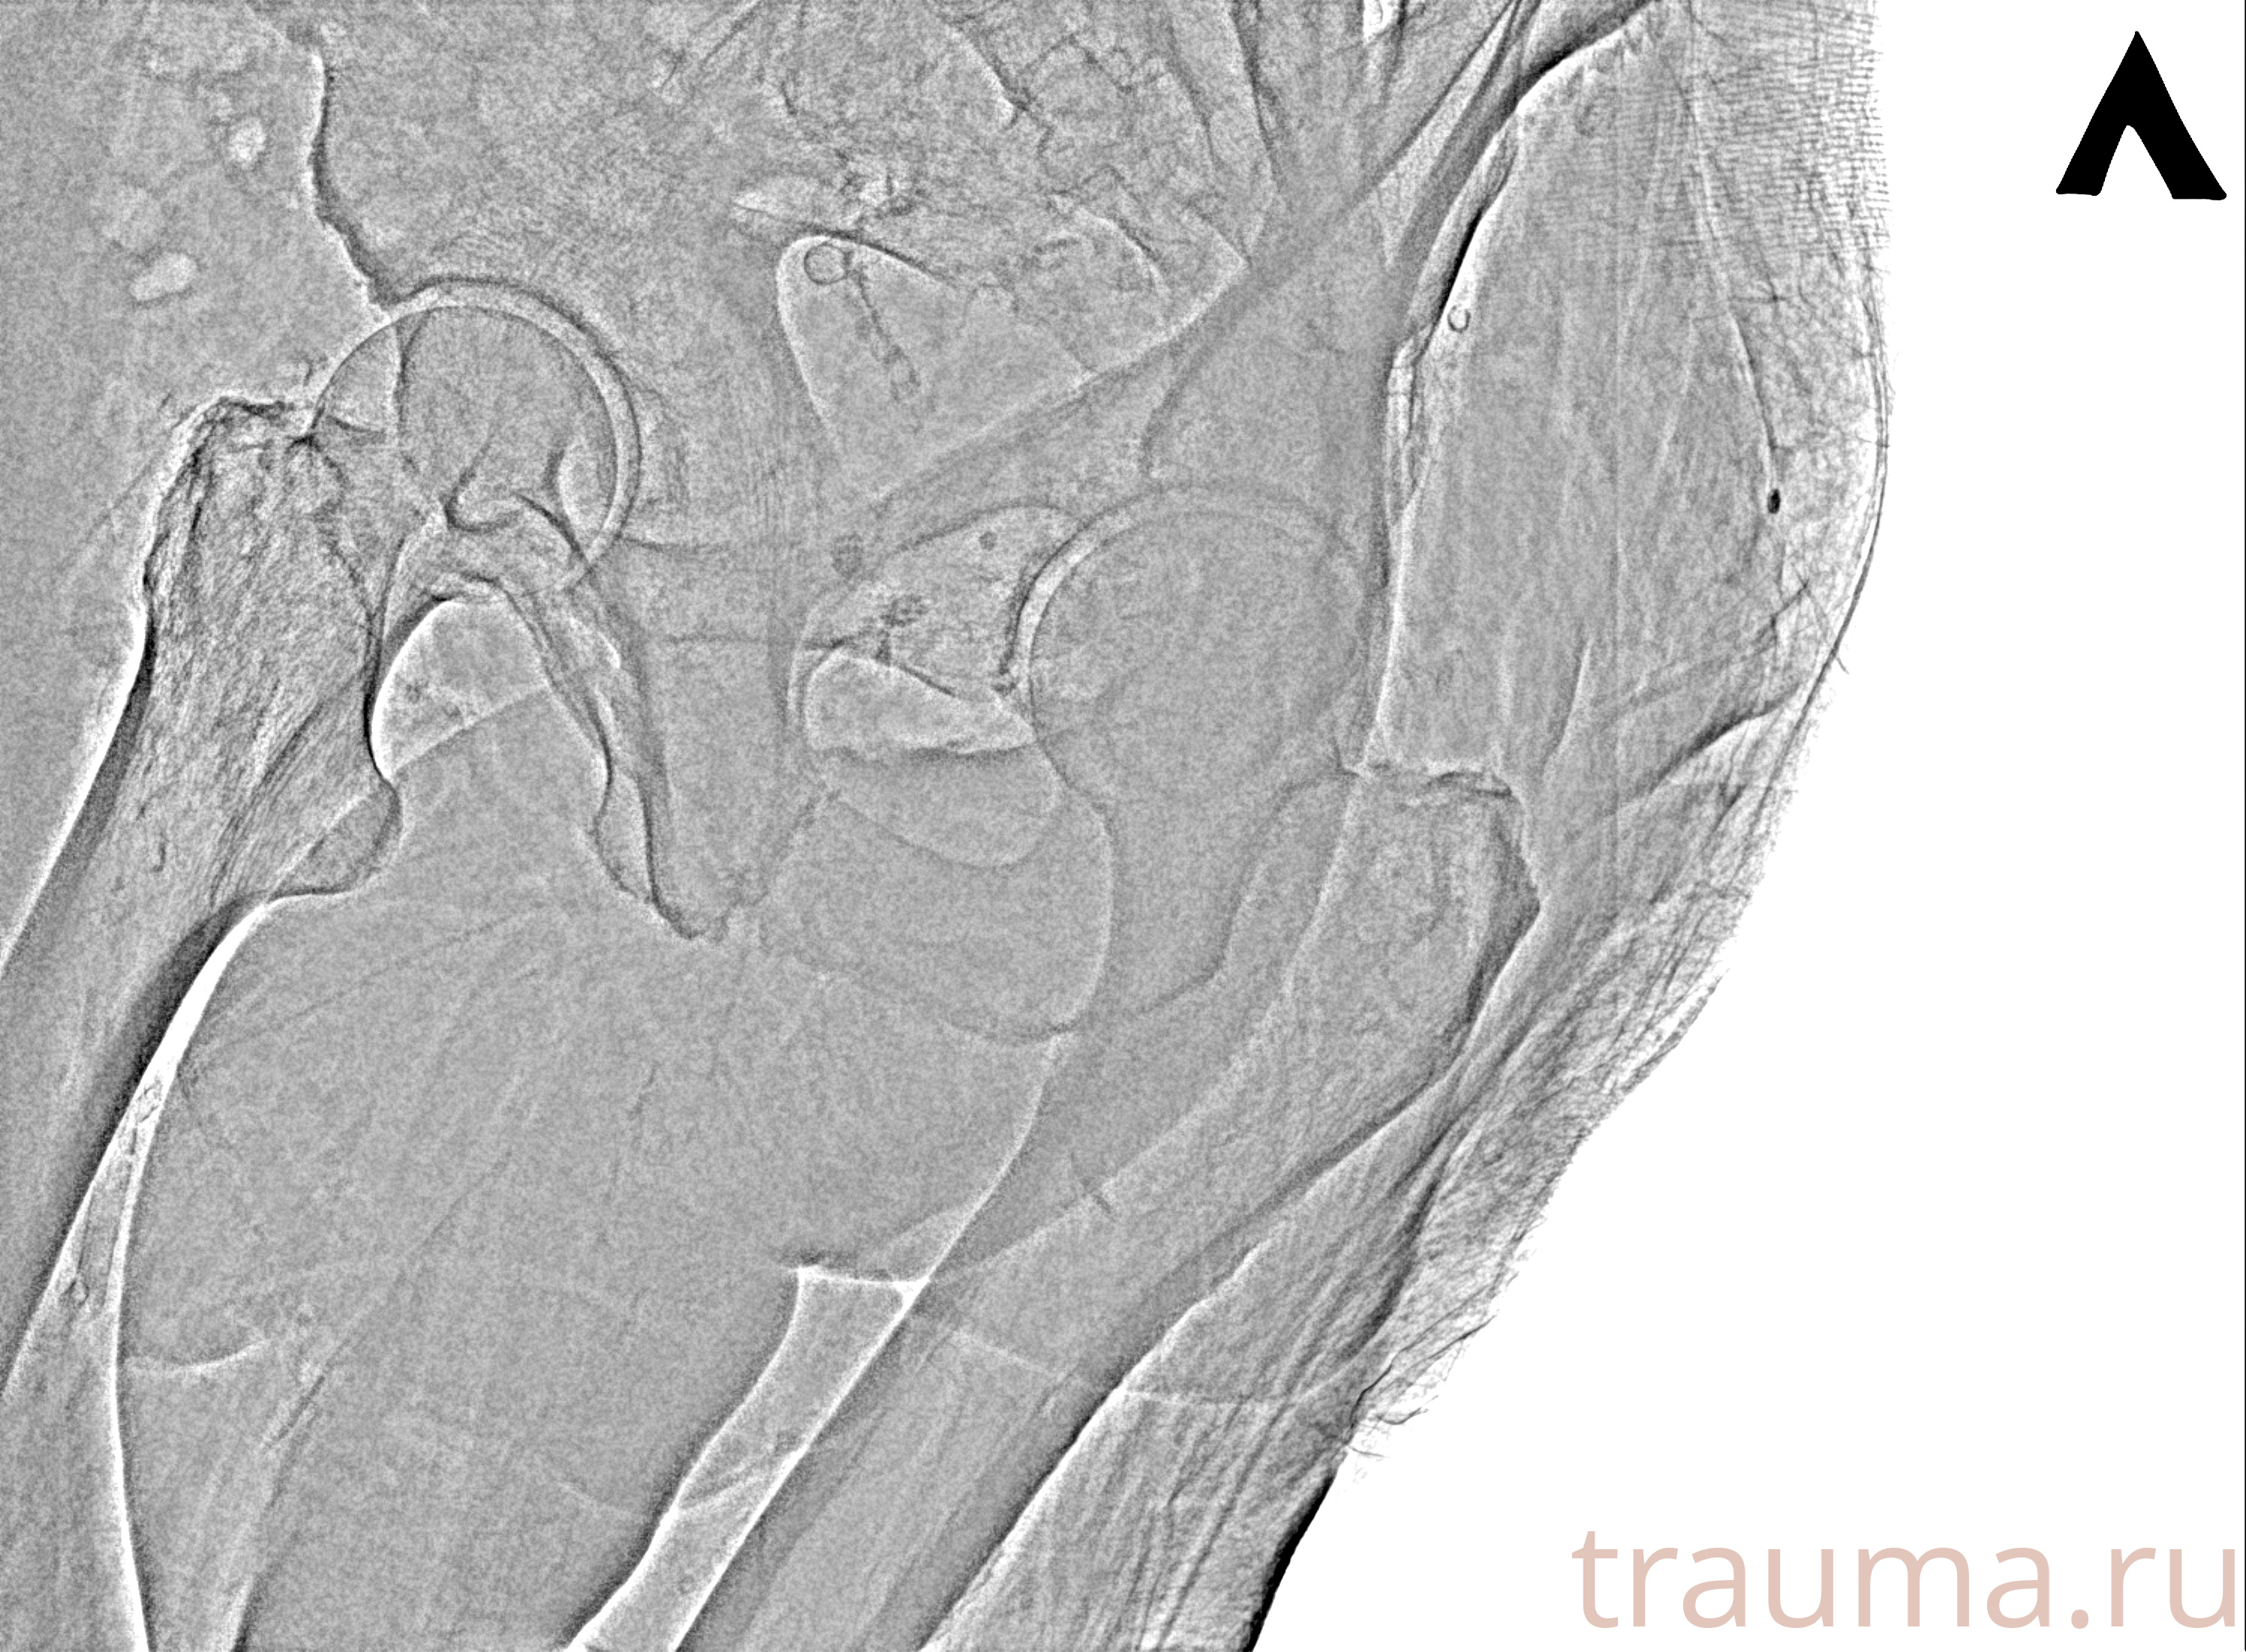

Рентген на дому: по вашему адресу приезжает врач-рентгенолог, травматолог-ортопед с мобильным рентгеновским аппаратом, проводит диагностику травмы или заболевания, делает необходимые рентгенограммы, дает рекомендации по дальнейшему лечению. Получить качественные снимки в домашних условиях возможно благодаря уникальной методике, разработанной МосРентген Центром для института  Склифосовского